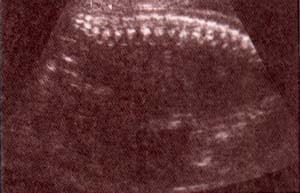

| fig 25. – (a).tercer trimestre corte transversal. 36 semanas. las flechas indican los núcleos de osificación |